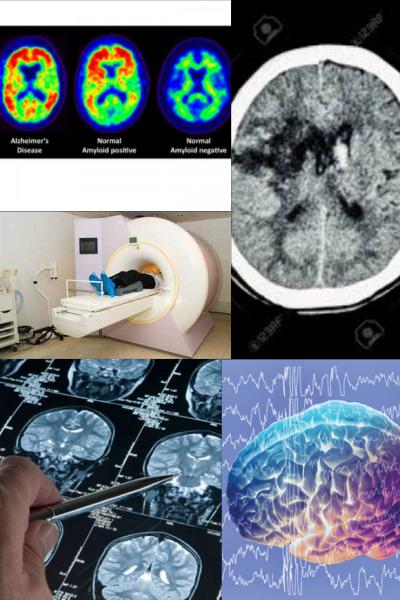

Kafatası içindeki her türlü yapı ve oluşum bozukluklarını saptamaya yönelik tanı yöntemi. Beyin taraması için pek çok araç ve yöntem geliştirilmişse de, en etkilileri izotop taraması ve bilgisayarlı eksenel tomografidir.

Beyin dokularına yerleşen radyoaktif madde bozunuma uğrayarak (parçalanarak) gamma ışınları salmaya başlar. Bu ışınlar, başın üstünde ileri geri gezdirilen ışıltı sayacı ya da gamma kamerası gibi bir ışın saptama aygıtıyla ölçülür. Beynin belirli bir bölgesindeki radyoaktif madde derişikliğine bakarak, kafatası içindeki bir oluşum bozukluğunun varlığı, biçimi, hatta boyutları saptanabilir. Bilgisayarlı beyin tomografisinde, beyin, değişik açılardan gönderilen X (röntgen) ışınlarıyla taranır.

Hastanın başının çevresinde döndürülen bir X ışını kaynağından kısa aralıklarla çıkan ışınlar, bu kaynakla birlikte dönmekte olan elektronik bir saptayıcı tarafından alınır ve gerekli veriler bir bilgisayara aktarılır. Bilgisayar, birçok taramanın sonuçlarını çözümleyip birleştirerek beyin kesitinin ayrıntılı bir görüntüsünü oluşturur. Böyle bir dizi görüntünün yardımıyla, beyindeki urların, apselerin, kan pıhtılarının ve geleneksel röntgen teknikleriyle saptanması güç olan başka bozuklukların yeri kolayca belirlenibilir.